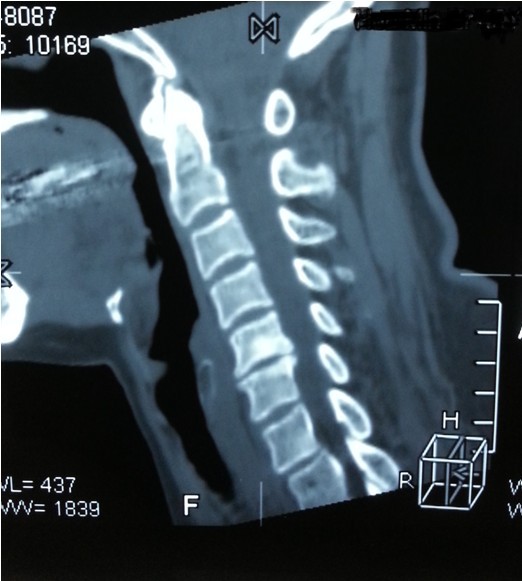

我院副院長兼脊柱科主任劉志安詢問病史后,詳細查體并攝片,發(fā)現(xiàn)患者是頸椎間盤突出,骨質增生,壓迫頸椎神經,引起頸肩部酸脹難忍,雙手麻木乏力,若不盡快處理,癥狀將進一步加重,建議患者盡早手術治療,否則將喪失最后的手術時機,有致癱瘓的可能。

一開始,處于對手術以及住院費用的恐懼,患者要求保守治療,可是如此嚴重的椎間盤突出,保守治療根本無法解除對頸椎的神經的壓迫。劉副院長詳細向患者講述其病情起因,發(fā)展,變化,轉歸,并表示,患者頸椎手術總費用預計在5萬以內,報銷后自費約4萬左右,考慮患者家庭困難,可聯(lián)系紅十字基金會予以適當?shù)难a貼,考慮再三,最終患者選擇到我院手術治療。手術結束后,患者慢慢開始恢復,頸肩部酸脹不適癥狀消失,雙手麻木乏力癥狀較術前大為緩解,兩周后出院,患者及家屬對手術治療效果,醫(yī)生護士服務態(tài)度,以及花了3萬元就解決困擾多年的疾病均表示非常滿意。